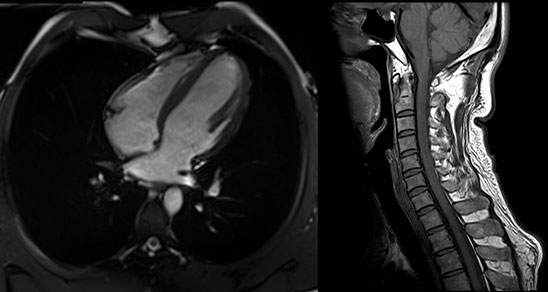

MAGNETOM Spectra 3.0T新一代聚能光谱磁共振

MAGNETOM Spectra 3.0T聚能光谱磁共振